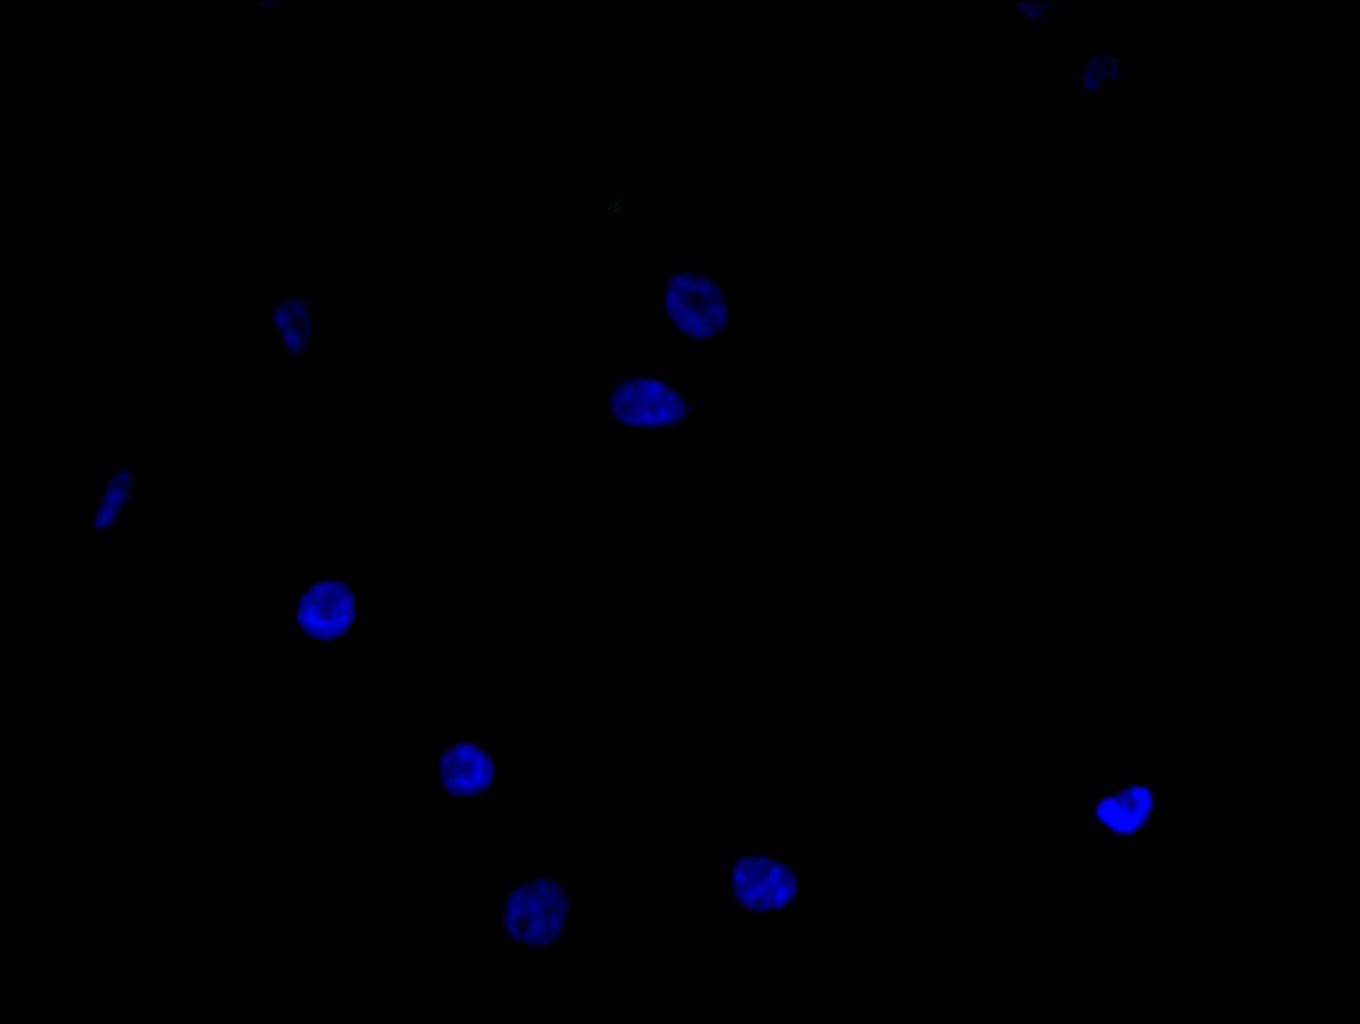

Immunofluorescence staining of MCF-7 cell with 5% goat serum, counter-stained with DAPI. The cells were fixed in 4% formaldehyde and blocked in 10% normal Goat Serum. The cells were then incubated with the antibody overnight at 4C. The secondary antibody was Alexa Fluor 488-congugated AffiniPure Goat Anti-Rabbit IgG(H+L).

Immunofluorescence staining of HepG2 cell with 5% goat serum, counter-stained with DAPI. The cells were fixed in 4% formaldehyde and blocked in 10% normal Goat Serum. The cells were then incubated with the antibody overnight at 4C. The secondary antibody was Alexa Fluor 488-congugated AffiniPure Goat Anti-Rabbit IgG(H+L).